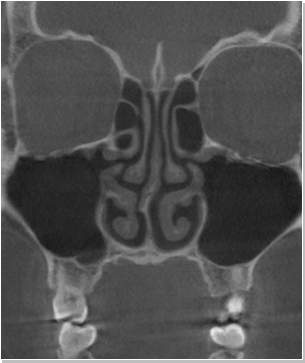

비염

비중격만곡증

축농증

비염 코성형은 코막힘, 재채기, 가려움증을 유발하는 코 질환과 휜코, 매부리코 등 못난 코 모양을 한 번에 개선시켜주는...